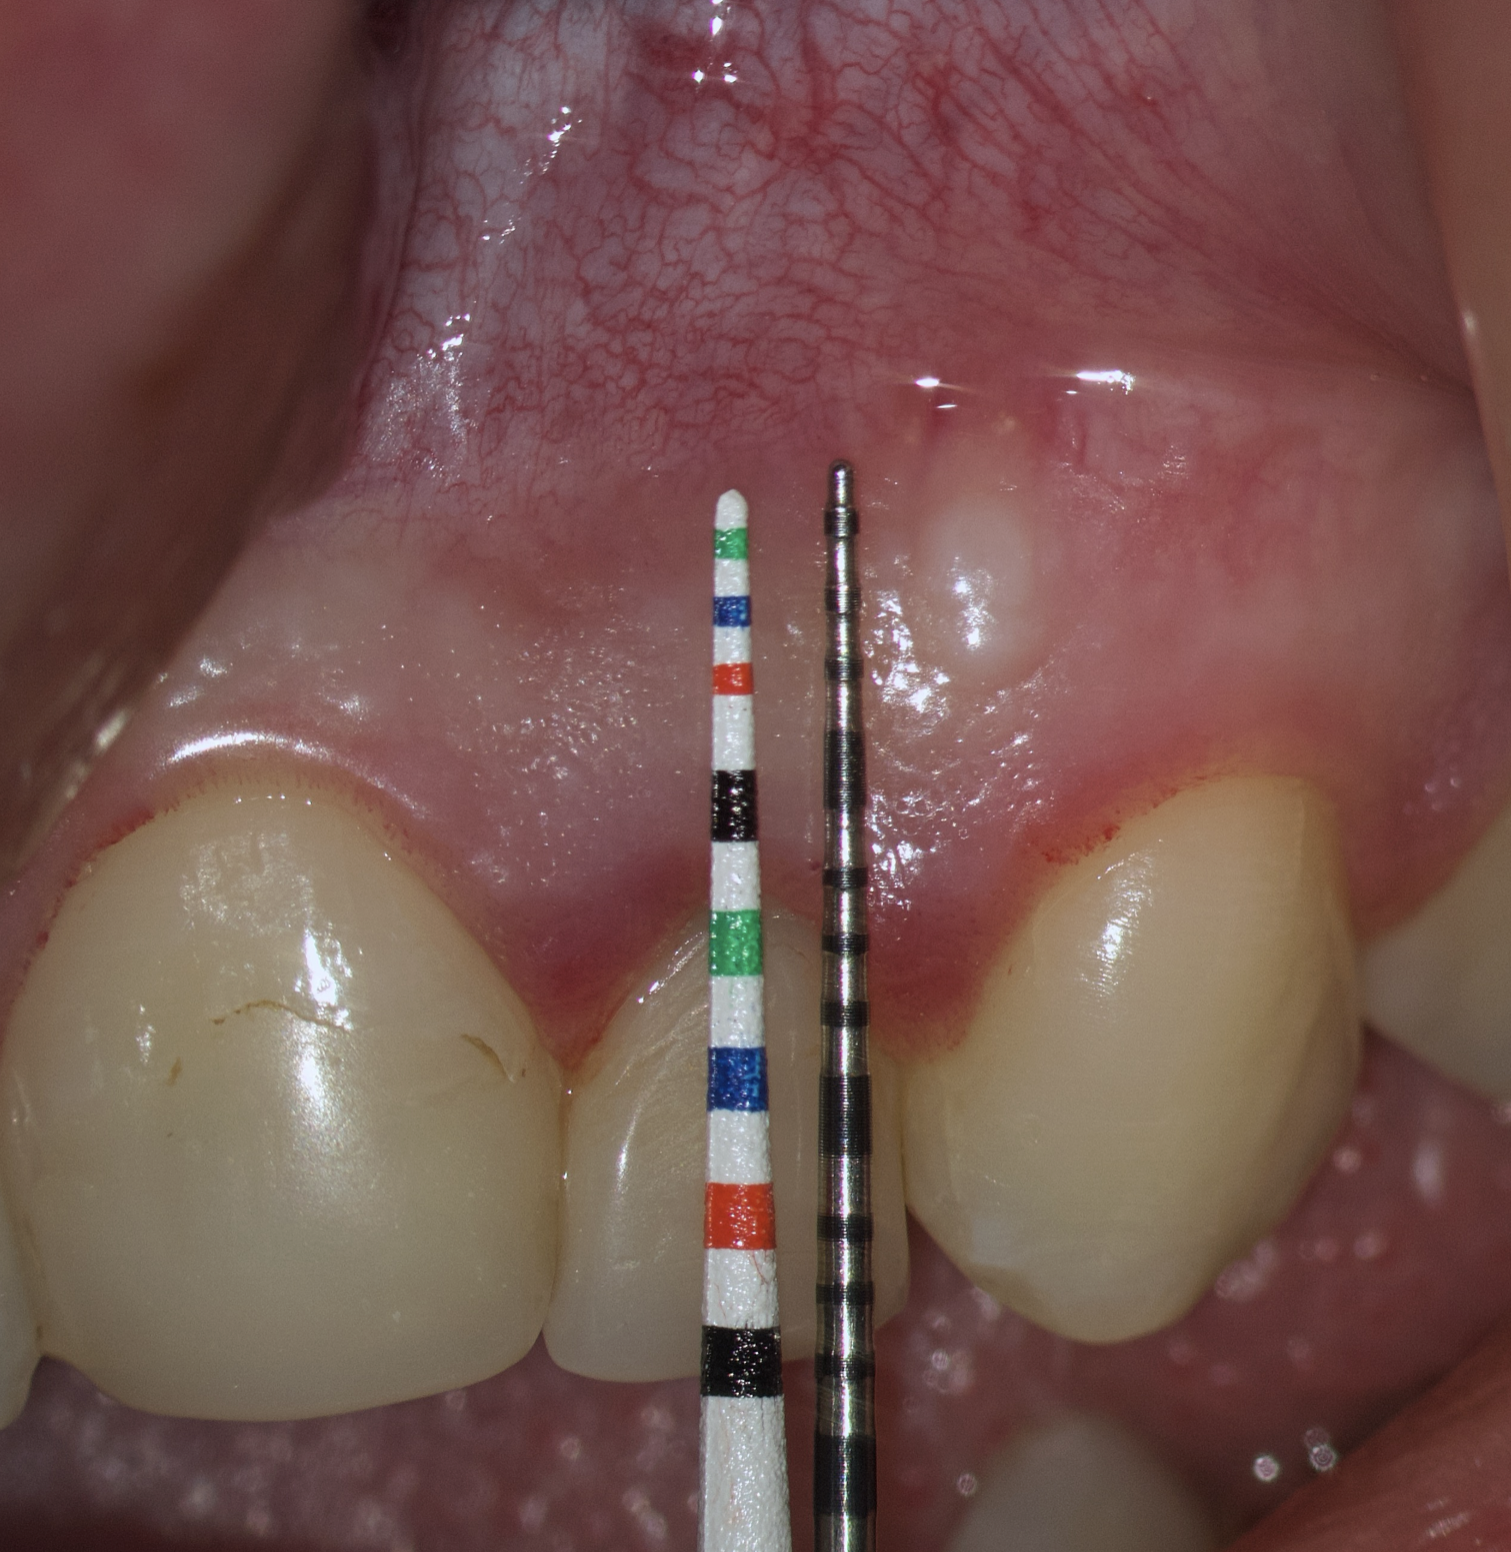

The most popular paramarginal or submarginal flap is the one designed by Clifford Ochsenbein and Raymond G. Luebke (1974) [4, 5]. The Ochsenbein-Luebke flap is formed by a scalloped horizontal sub-marginal incision placed within the attached gingiva, which follows roughly parallel to the contour of the gingival margin. The horizontal incision continues with two vertical releasing incisions [6]. These vertical incisions extend from a point 1 to 2 mm short of entering the mucobuccal fold to a point on the attached gingiva approximately 3 to 5 mm above or below the marginal gingiva and the sulcus depth (Figs 1 and 2) [7, 8].

The submarginal flap is only to be used, when there is a broad zone of attached gingiva with a minimum of 2 mm [9]. The width of the attached gingiva is then calculated on the basis of the distance from the base of the sulcus to the linea girlandiformis (mucogingival junction) [6]. Consequently, the incision must be placed at least 2 mm from the depth of the gingival sulcus. Extensive periodontal probing should be done to establish the depth of the gingival sulcus before the incision is made [10]. Periodontal probing should be conducted not only around the causative tooth but also in the adjacent teeth.

Sometimes the frenulum of the upper lip is massive and for avoid its dissection, it is permissible to perform a submarginal flap with one vertical incision located more distally. It is worth recognizing that this approach is applied to a root with medium length on which microsurgery is performed (Figs 3 and 4).